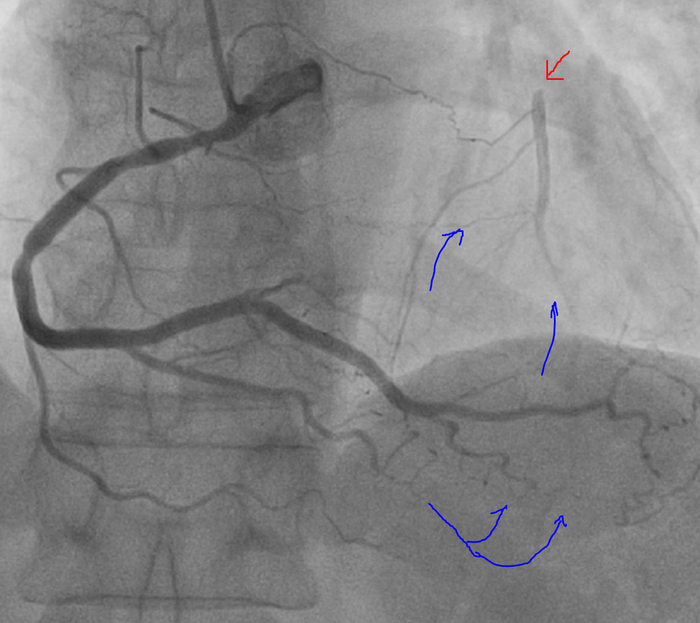

Снимаем правую коронарную артерию:

Сразу видно, что с левой коронарной артерией большие проблемы, по видимому закрыта передняя межжелудочковая артерия (красная стрелка). Правая тоже не лучшего качества - мультифокусное поражения, но без значимого стенозирования.